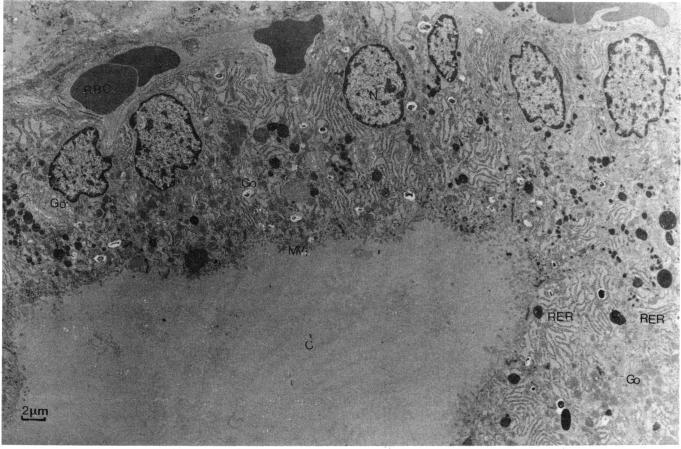

The effects, over periods from 3 days to 9 months of administration, of diets containing di-2-ethylhexyl phthalate are very similar to those observed in rats administered diets containing hypolipidemic drugs such as clofibrate. Changes occur in a characteristic order commencing with alterations in the distribution of lipid within the liver, quickly followed by proliferation of hepatic peroxisomes and induction of the specialized P-450 isoenzyme(s) catalyzing omega oxidation of fatty acids. There follows a phase of mild liver damage indicated by induction of glucose-6-phosphatase activity and a loss of glycogen, eventually leading to the formation of enlarged lysosomes through autophagy and the accumulation of lipofuscin. Associated changes are found in the kidney and thyroid. The renal changes are limited to the proximal convoluted tubules and are generally similar to changes found in the liver. The effects on the thyroid are more marked. Although the levels of thyroxine in plasma fail to about half normal values, serum triiodothyronine remains close to normal values while the appearance of the thyroid varies, very marked hyperactivity being noted 7 days after commencement of treatment, this is less marked at 14 days, but even after 9 months treatment there is clear cut evidence for hyperactivity with colloid changes which indicate this has persisted for some time. Straight chain analogs of di-2-ethylhexyl phthalate, di-n-hexyl phthalate and di-n-oxtyl phthalate differ entirely in their short-term effects on the liver and kidney but have similar effects on the thyroid. The short-term in vivo hepatic effects of the three phthalate esters can be reproduced in hepatocytes in tissue culture. All three phthalate esters, as well as clofibrate, have early marked effects on the metabolism of fatty acids in isolated hepatocytes. The nature of these changes is such as to increase storage of lipid in the liver. A hypothesis is presented to explain the progress from these initial metabolic effects to the final formation of liver tumors.